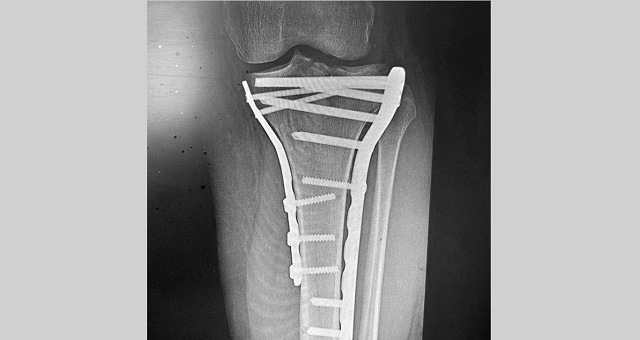

В Казани врачи горбольницы №7 прооперировали мужчину, который в результате падения с самоката получил многооскольчатый перелом верхнего суставного конца большеберцовой кости с разрывом боковых связок.

В ходе операции медики выполнили остеосинтез пластинами и винтами, а также восстановили связки коленного сустава. По словам медиков, самокат в последнее время стал популярным средством попадания в травматологическое отделение.

Фото: телеграм-канал «Травматология и ортопедия Татарстана»